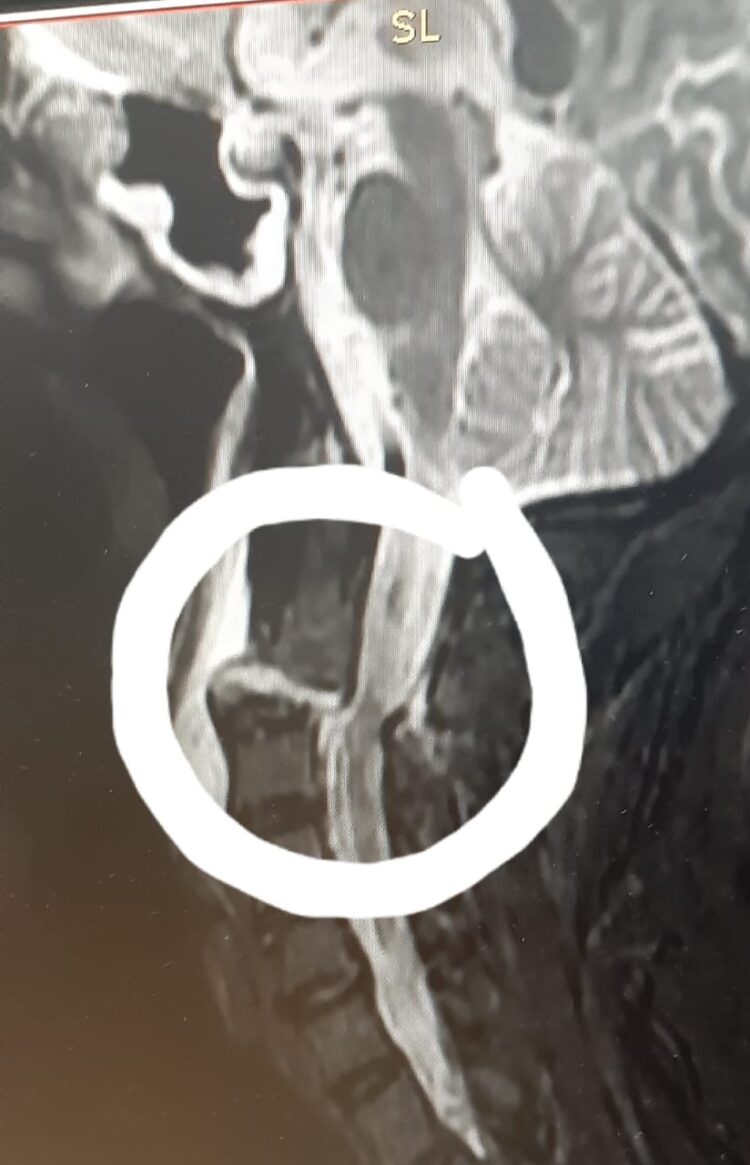

The MRI cervical spine revealed fracture dislocation of C2 over C3 vertebrae. This was a complex cervical spine injury which can be fatal or crippled patient if not treated, said Dr. Vineet Saggar.